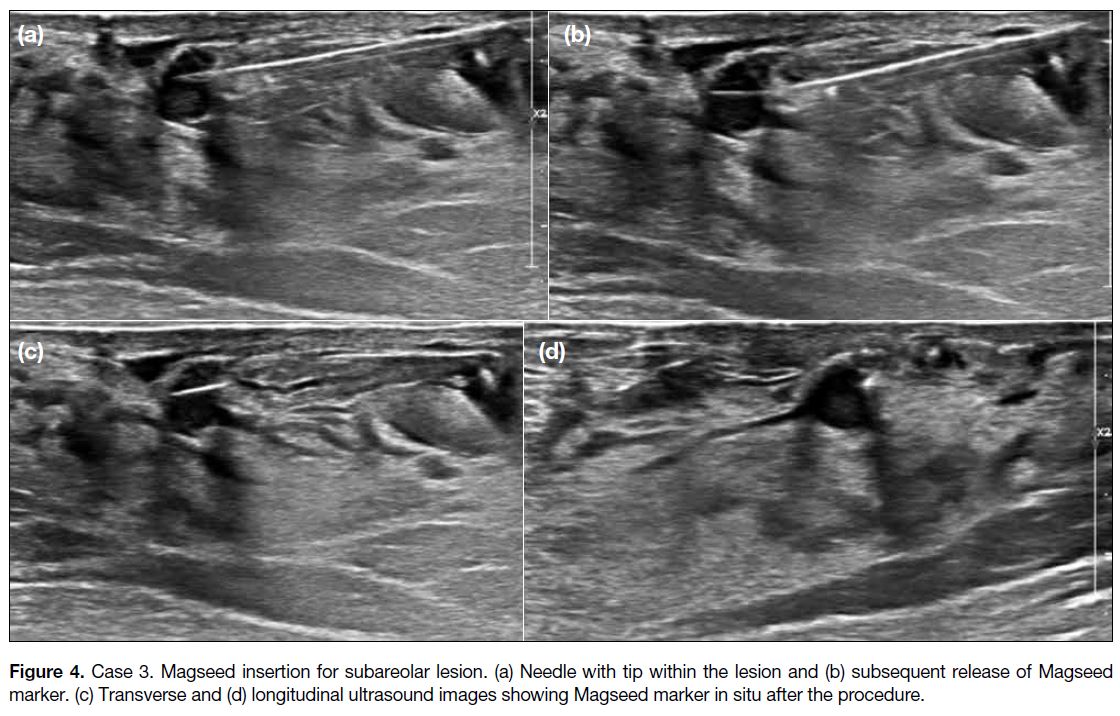

Case 3

A 45-year-old woman presented with a 3-year history

of bilateral mastalgia and breast imaging from another

centre that identified a small right breast 12 o’clock

position subareolar complex cystic lesion measuring

5 × 5 × 6 mm (Figure 3). Biopsy of the lesion suggested

intraductal papilloma and surgical excision was planned.

In the interim, follow-up breast imaging at another centre

identified another lesion in the same breast, 12 o’clock

position, 3 cm from the nipple, measuring 3 × 3 × 5 mm

(Figure 3). Biopsy pathology also showed intraductal

papilloma. The patient underwent preoperative

localisation of these two lesions with Magseed (Figures 4 and 5). Magseeds were inserted into both lesions,

with inter-Magseed distance measured to facilitate

surgical localisation. Lumpectomy was performed for

both lesions 14 days after Magseed localisation. Two

spikes corresponding to the two Magseed markers

were detected on Sentimag intra-operatively. The final

pathology report for the surgical specimen confirmed

intraductal papilloma with usual ductal hyperplasia.

Figure 4. Case 3. Magseed insertion for subareolar lesion. (a) Needle with tip within the lesion and (b) subsequent release of Magseed marker. (c) Transverse and (d) longitudinal ultrasound images showing Magseed marker in situ after the procedure.